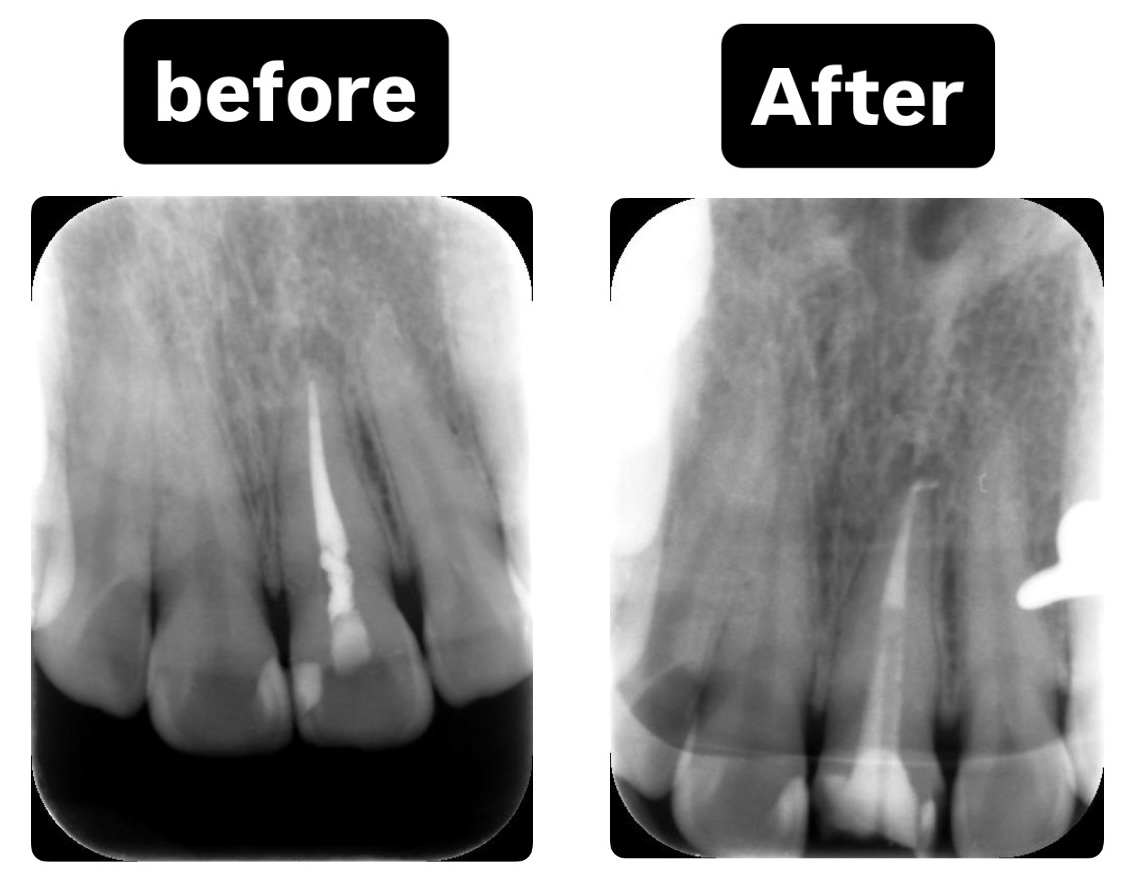

CASE2:【抜歯回避】他院で抜歯宣告された重度根尖病変の保存治療

主訴:歯が浮くような違和感(再根管治療)

歯が浮いている感じがあり、他院で抜歯と言われた

診断:CTによる精密検査で見つかった複雑な感染源

CTでしっかりと診断を行ったところ、とても深刻な状況でした。根管治療が重要ですが、それだけでは完全な治癒が望めない場合もあり、歯槽骨の再生を促す外科的処置が必要になることもあります。

こちらの患者様のように、歯槽骨のダメージが大きい症例では、根管内の感染と歯肉溝内の感染が両方の原因となっていることが多いですね。

根尖病変によりCT上で黒く写っていた部分が白っぽくなっているのがわかりますか?

溶けていた部分の歯槽骨が回復しているということです!

また、上顎洞の肥厚は収まり、頬側の歯槽骨もくっきり映っています。予想以上に歯槽骨が回復しているので、今後外科的処置をしなくても良いのではないかと判断しました。大きなダメージがあった歯なので補綴物を入れた後も欠かさずに経過観察を行い、少しでも長くご自身の歯で生活して頂きたいと思います。